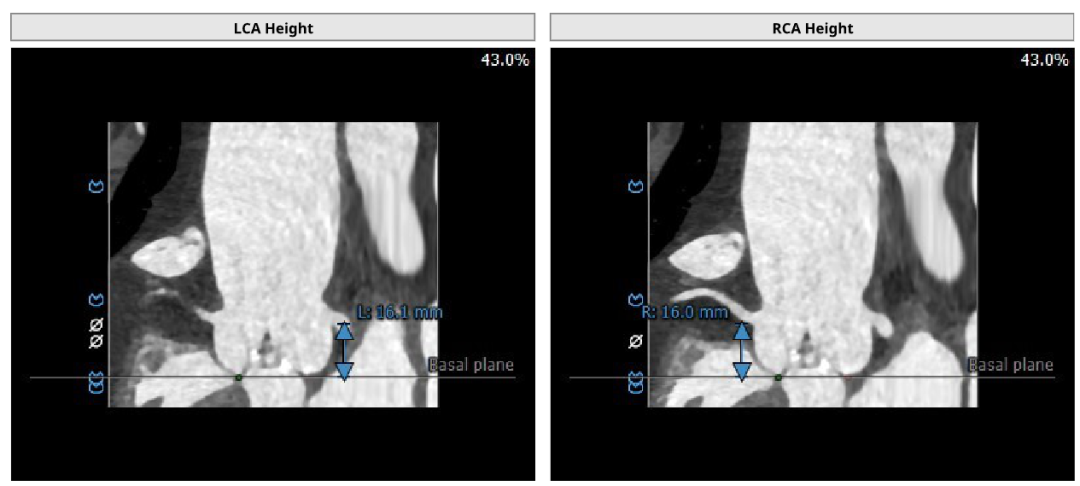

患者女性,77岁,Type 0二叶瓣。主动脉瓣重度狭窄,术前平均跨瓣压差80mmHg,峰值流速5.6m/s。瓣叶钙化,瓣环面积径21.1mm。左冠高度16.1mm,右冠高度16.0mm。外周入路可见钙化,内径尚可。

术前评估